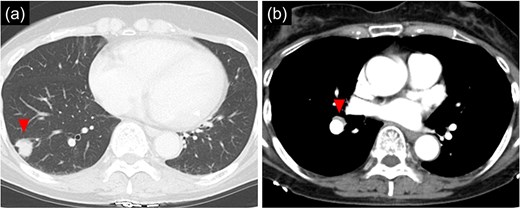

Bronchoscopy after intubation revealed an orifice of the BD in the cartilage of the right main bronchus with two rings below the carina (Fig. 2). First, a lower mediastinal lymph node dissection and BD were performed. The area around the BD was prone to bleeding and the lymph nodes were in close contact with each other (Fig. 3), making it difficult to separate them from the BD. After identifying and exposing the stalk of a BD, ligation of the diverticulum with ENDOLOOP® PDS II Ligature allowed for control of bleeding and the lymph nodes could be safely removed from the BD (Video 1).

Intraoperative images of the inferior mediastinal region. (a) Image of dissecting the bronchial diverticulum and mediastinal lymph nodes. (b) Image of a bronchial diverticulum after ENDOLOOP® PDS II Ligature ligation. Arrowhead: bronchial diverticulum.

After lymph node dissection was complete (Fig. 3), the BD was additionally ligated. The #11i LN was enlarged but without invasion, and there was no lymph node metastasis on frozen pathology. Following a conventional right lower lobectomy, the BD and lower lobe bronchial stumps were covered with pericardial fat tissue. The patient was discharged without postoperative complications. No lymph node metastases were found pathologically in the other dissected lymph nodes, and the diagnosis was p-T1bN0M0 stage IA2. Chest CT 6 months after the operation showed no recurrence of lung cancer; however, air was detected in the BD, suggesting an opening of the diverticulum.